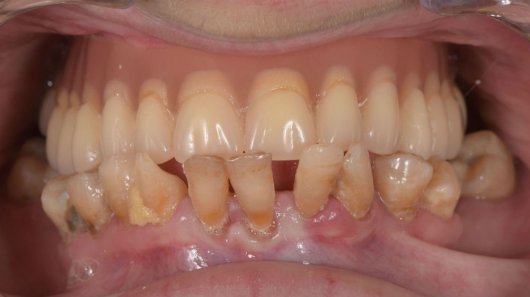

Montserrat presentaba una periodontitis grave en la arcada inferior y una prótesis en la arcada superior que necesitaba ser renovada. Después de un tratamiento periodontal para rehabilitar el hueso, se le colocaron 4 implantes zigomáticos y 6 implantes en la arcada inferior, así como prótesis definitivas en ambas arcadas.